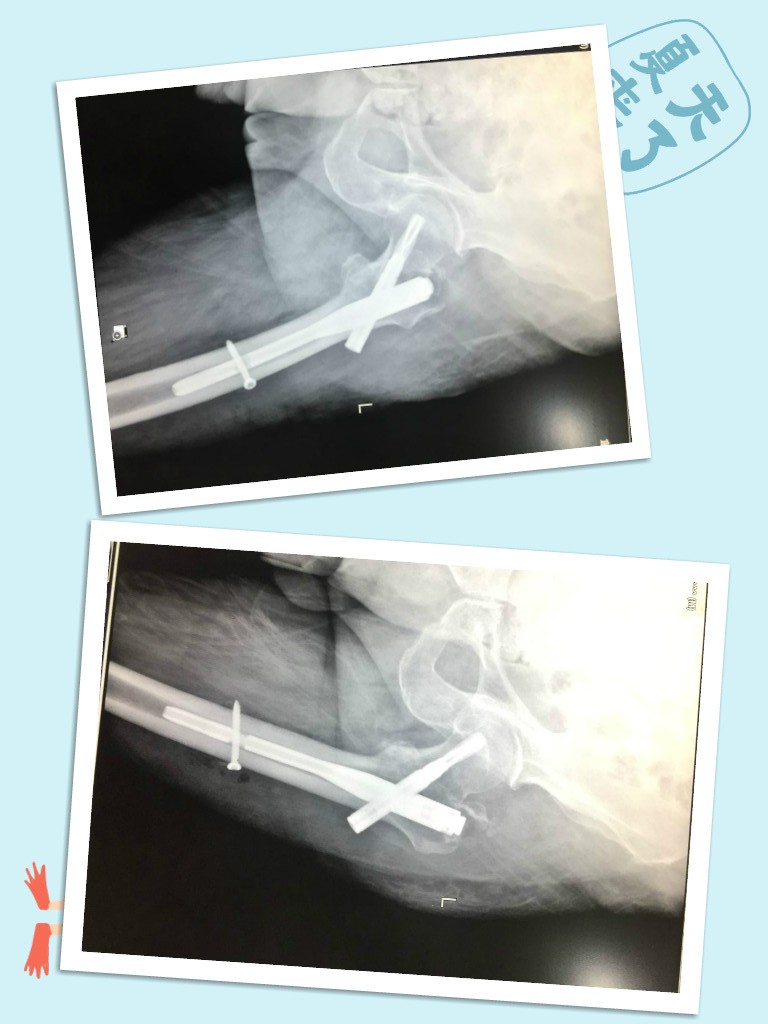

经过髋关节DR检查诊断为“左股骨粗隆间粉碎性骨折”

术前_meitu_6画圈.jpg

术后.jpg

入院不久,在宜宾民心创伤骨科医院骨科主任的带领下,医护团队为王大伯成功实施了左侧股骨粗隆间骨折pfna内固定术。